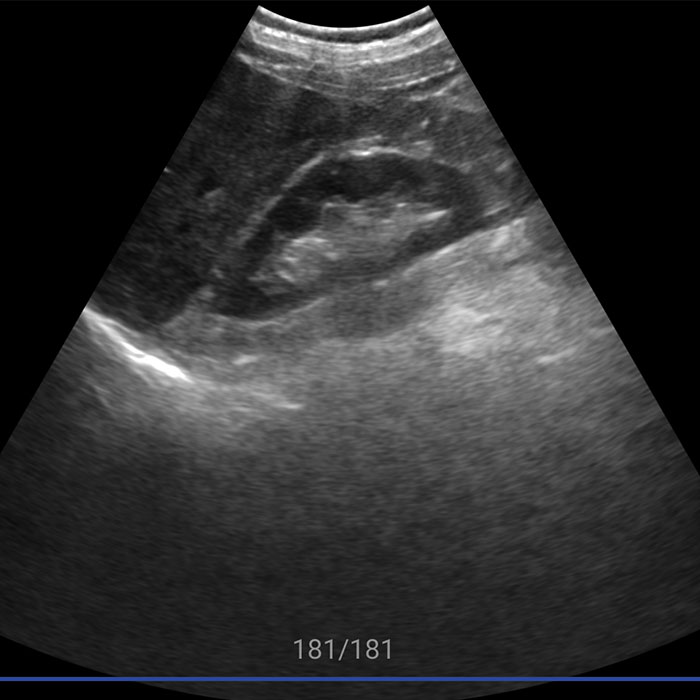

视网膜屏幕,超高分辨率。优异的图像,媲美大型超声。临床功能全面,覆盖全身

原始的超声图像像天书一样,除了专业超声医生谁都看不懂,新名医率先实现了针对超声实时动态图像的特定目标、多目标识别,准确率超过93%,超声AI数据集规模、识别准确率、移动端工程实现能力业内领先。

智能手持超声提供覆盖全身的优异图像